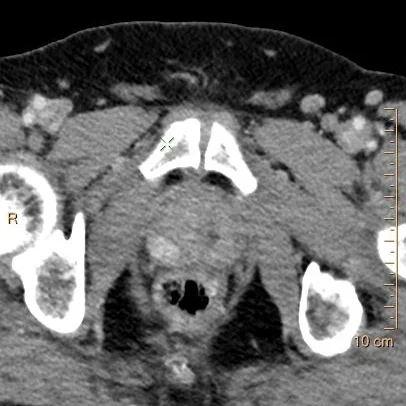

65 yo M presents with abdominal pain. Routine CT of the abdomen obtained, showing the usual cysts in kidneys and liver, diverticulosis and a mildly enlarged prostate. Look carefully, and there is a small enhancing nodule in the right posterior peripheral zone. This measures about 125 HU, as opposed to 75 HU in the left peripheral zone (standard deviation is about 15-20 HU). This is a ratio of about 1.66.

Conventional CT: Enhancing nodule in the right PZ of the prostate

Notice the difference in HU on conventional image: enough to be easily perceptible in this case, but will it be so on all cases?